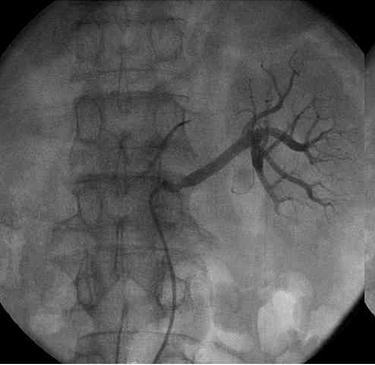

一侧肾脏的血管造影图

两侧肾脏的血管造影图